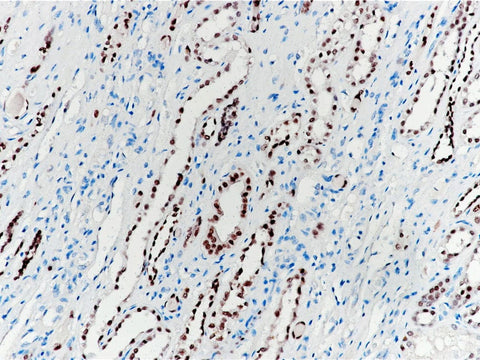

Pax-2 Monoclonal Antibody Stored at 2~8°C

Applications IHC-P

Cellular Localization nucleus

Tissue Specificity Kidney

Pax-2 is a member of Pax transcription factor family. Pax-8 and Pax-2 participate in the formation of renal organs. In non-tumor tissues, Pax-2 is expressed in glomerular wall epithelial cells, renal collecting duct cells, atrophic renal tubular cells, ovarian surface epithelial cells, fallopian tubes, endometrium, endometrium. In primary tumors, Pax-2 is mainly expressed in renal cell carcinoma and nephrogenic tumor. Recent studies have shown that Pax-2 can be used as an effective immunohistochemical marker for the judging of renal epithelial cell tumors and some gynecological tumors.